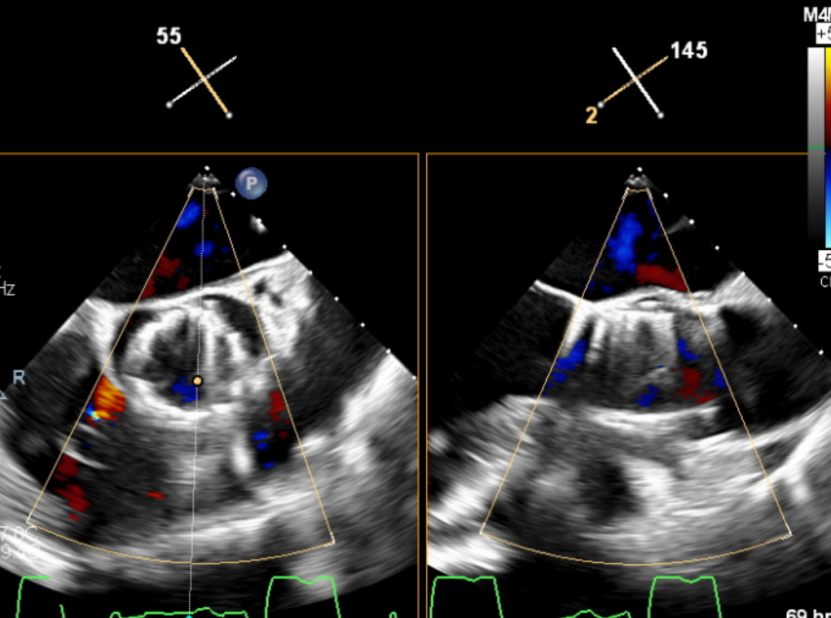

左室长轴切面可见流出道结构良好,短轴切面可见主动脉瓣大量反流。

(流出道结构观察)

(短轴切面观察)